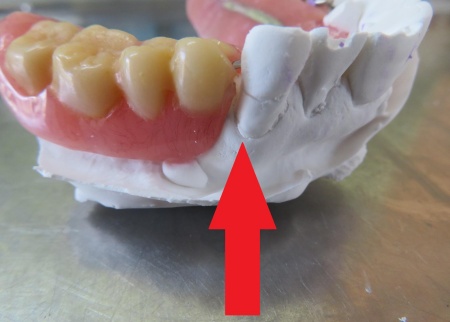

80代女性 部分入れ歯の金属バネを修理して再び使えるようにした症例

- 部分入れ歯

- 治療期間の目安 -

- 治療回数の目安 1回

-

治療費総額の目安

約1,000円

(保険診療1割負担)

治療のリスク

・着脱式のため、食後の清掃が必要です ・最初のうちは異物感があり、慣れるまで時間がかかる場合があります ・慣れるまでは、入れ歯の裏側の粘膜に傷ができる場合があります...

by.いとう歯科医院

2026/03/30